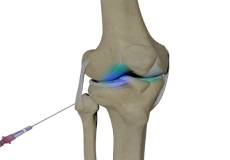

Combined Hyaluronic Therapy for the Knee

Combined hyaluronic therapy is the process of injecting hyaluronic acid (HA) along with platelet-rich plasma (PRP) into your knee to treat osteoarthritis.

Viscosupplementation

Viscosupplementation refers to the injection of a hyaluronan preparation into the joint. Hyaluronan is a natural substance present in the joint fluid that assists in lubrication. It allows the smooth movement of the cartilage-covered articulating surfaces of the joint.